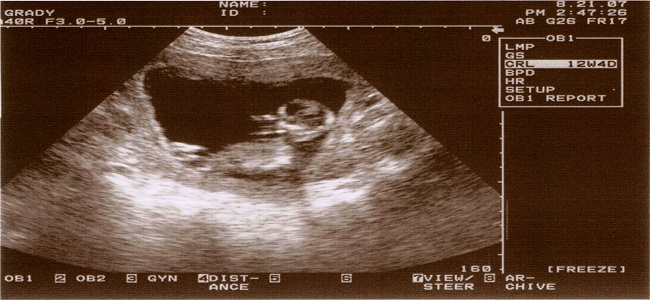

W 12 tygodniu ciąży organy płciowe dziecka są już wykształcone. Jednak nadal za wcześnie jest, aby określić czy będzie to chłopiec, czy dziewczynka.  Dziecko bardzo dużo się porusza. Posiada już odruch ssania i chętnie połyka wody płodowe. Ma już kubki smakowe, więc czuje smak potraw jedzonych przez mamę. Wody płodowe przybierają smak tego, co je kobieta. Serce dziecka bije szybko, około 160 razy na minutę. Dziecko mierzy około 6-7 cm i waży około 10-13 g.